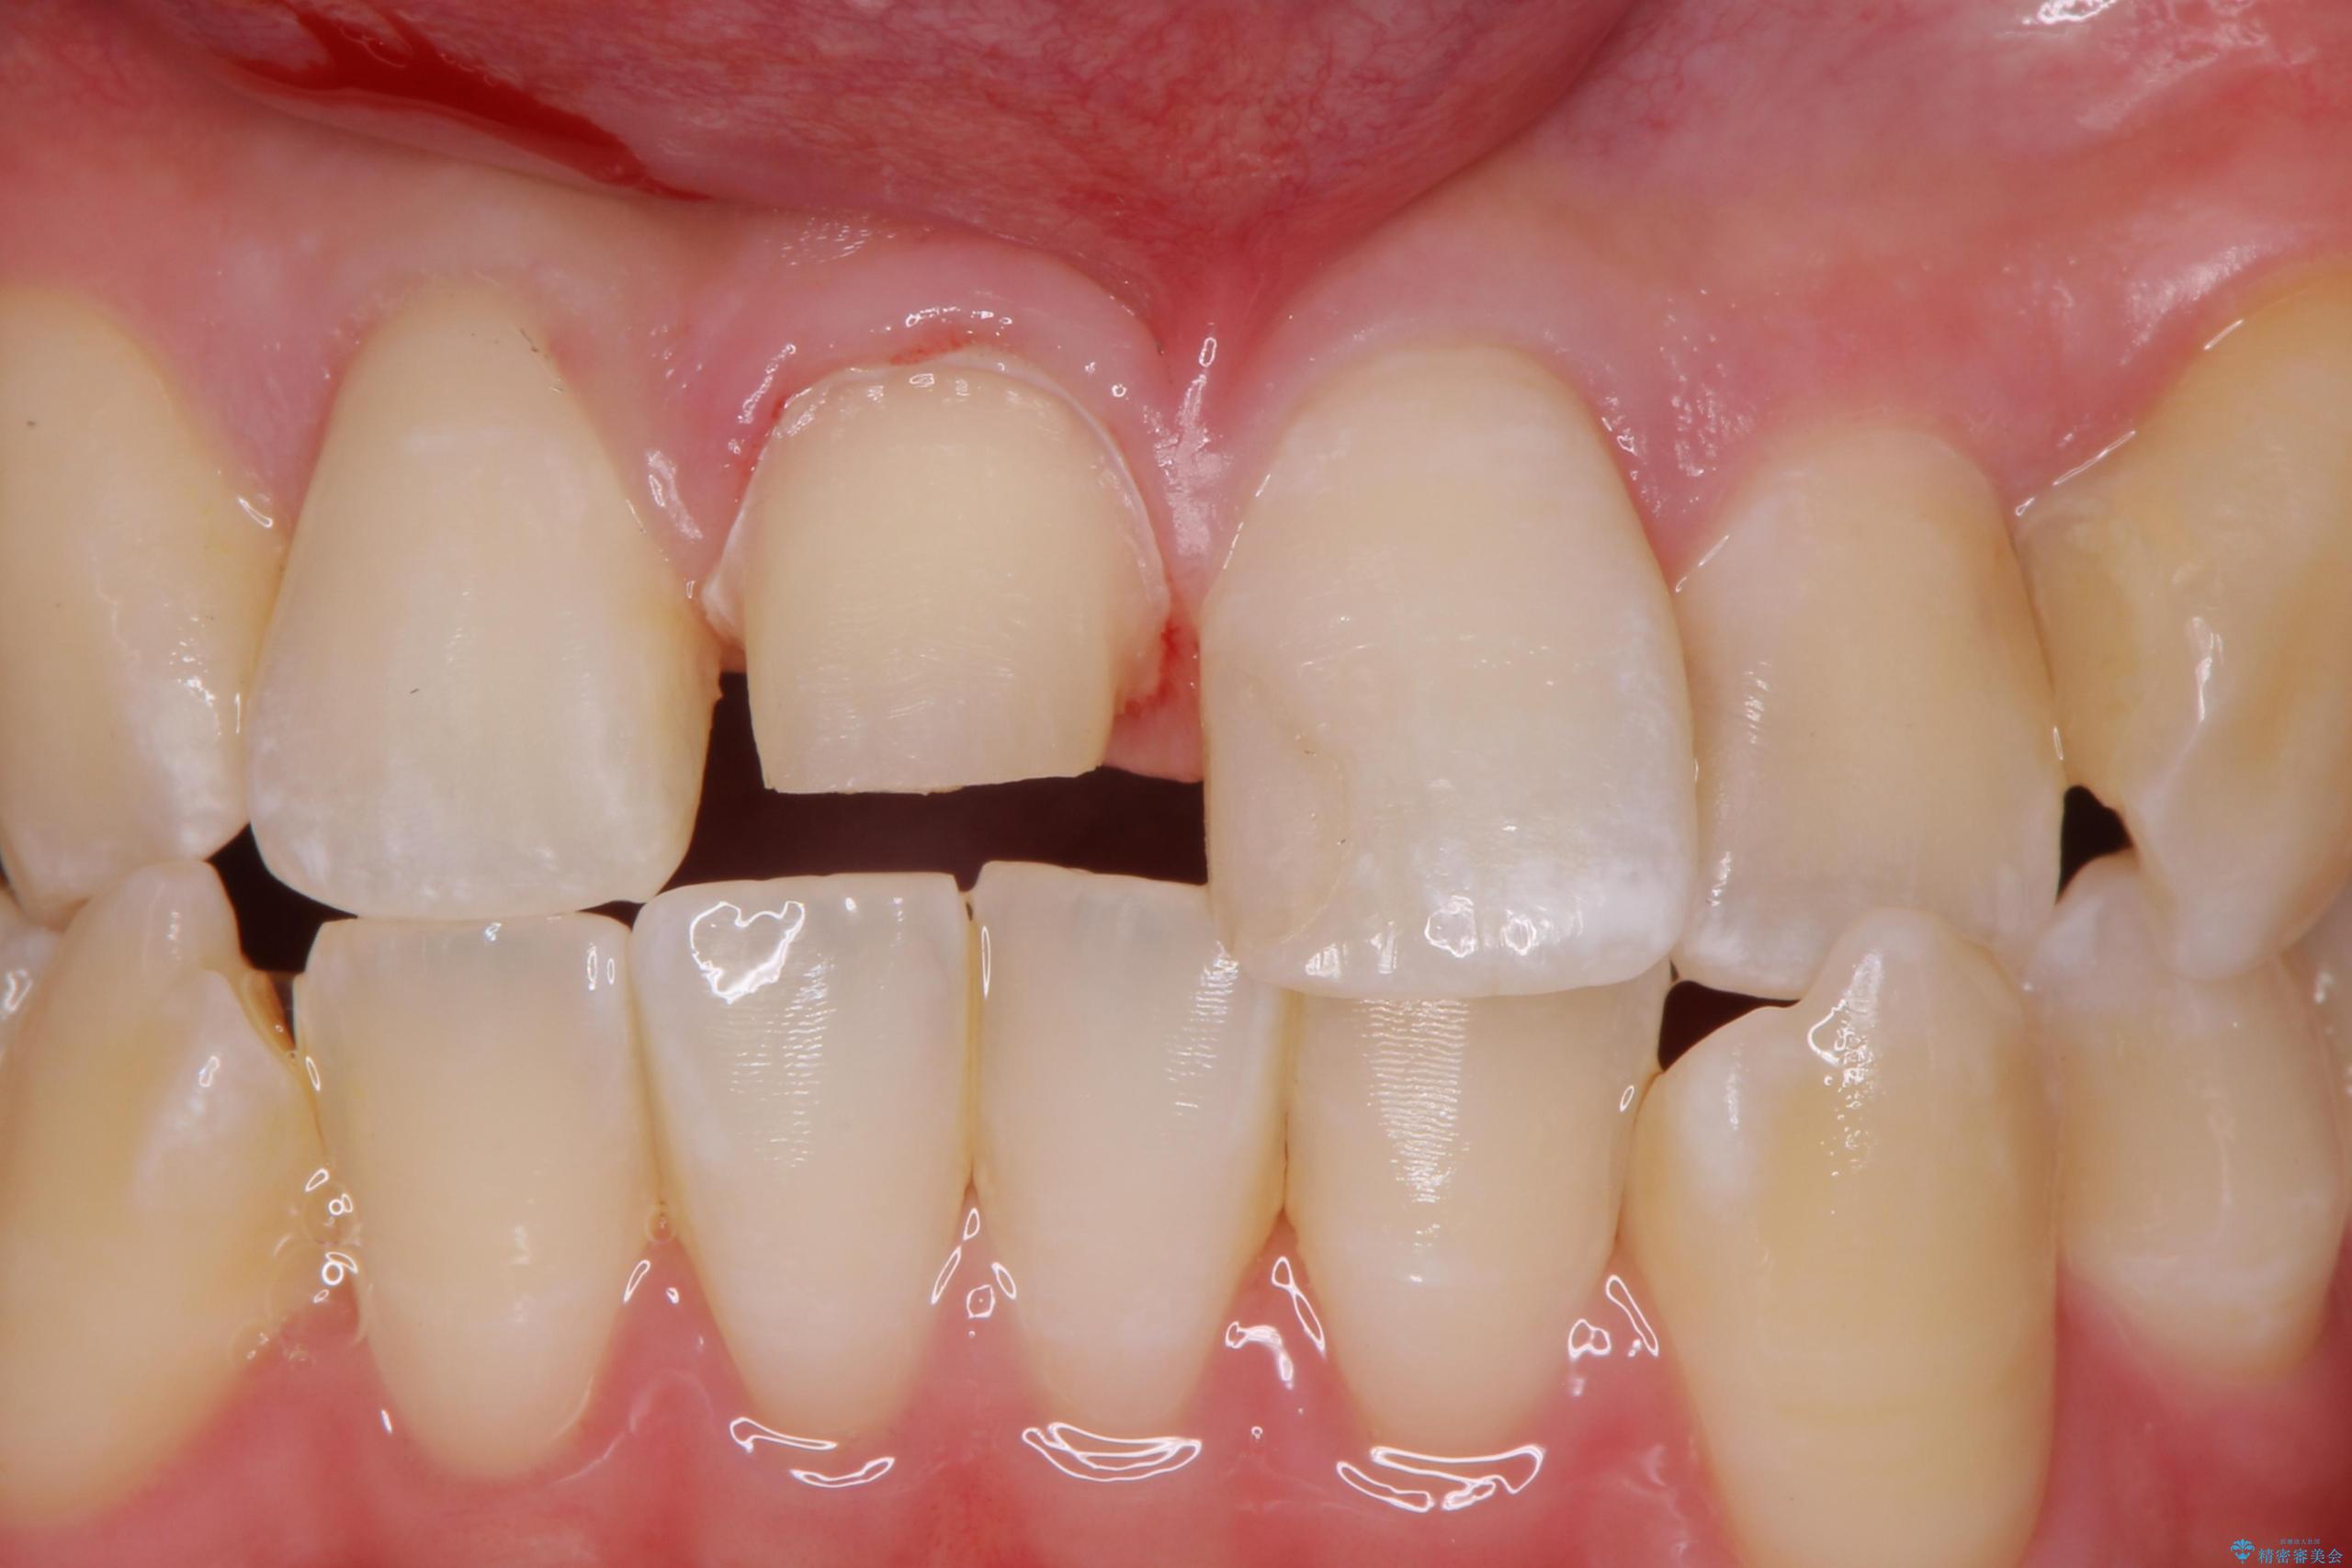

- 前歯のかぶせ物の色が気になるとのことで来院された患者様です。

セラミッククラウンで作り変えていきます。

- 右上1: 仮歯/11,000円、ジルコニアクラウン(スタンダード)/121,000円 合計132,000円(税込)費用は治療当時の料金となります